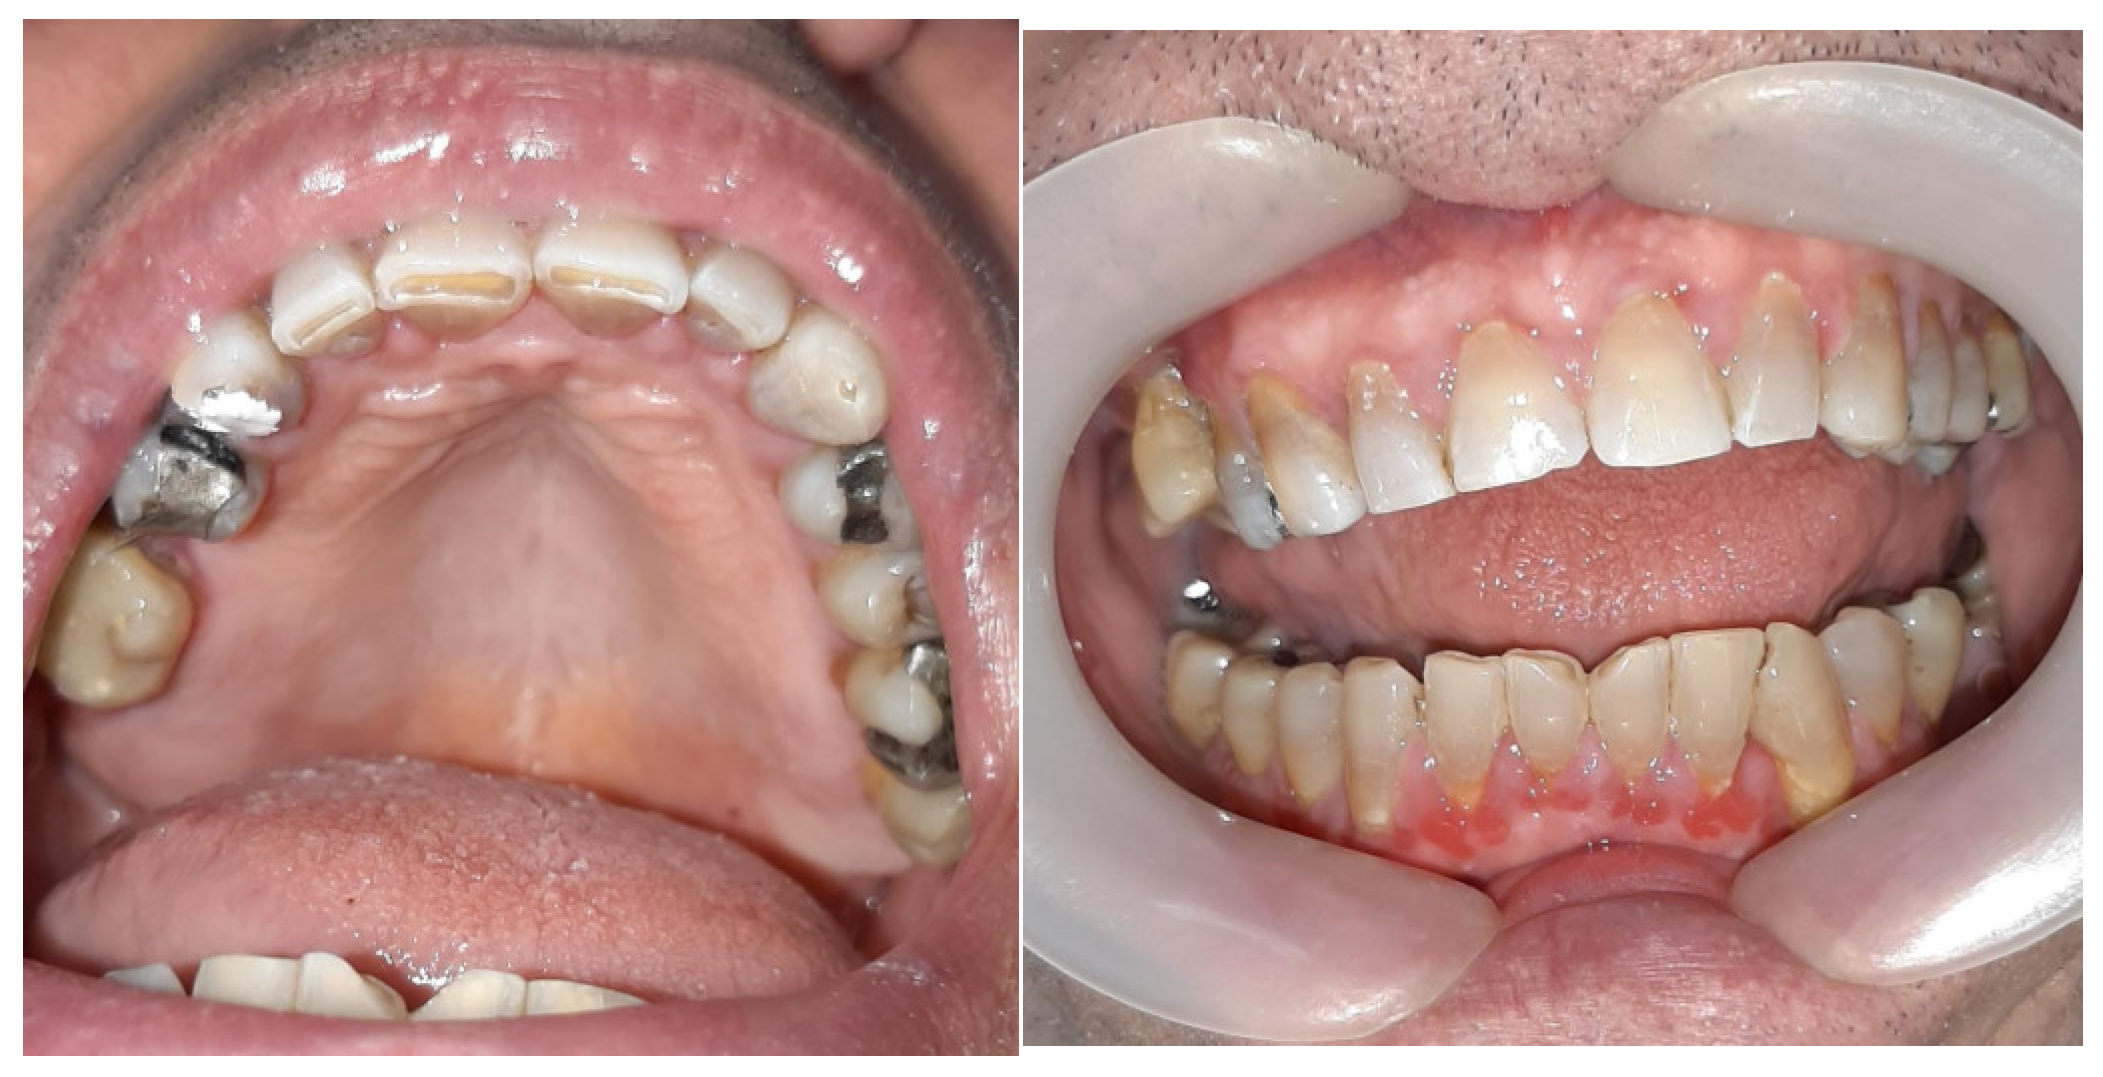

2. Case Presentation